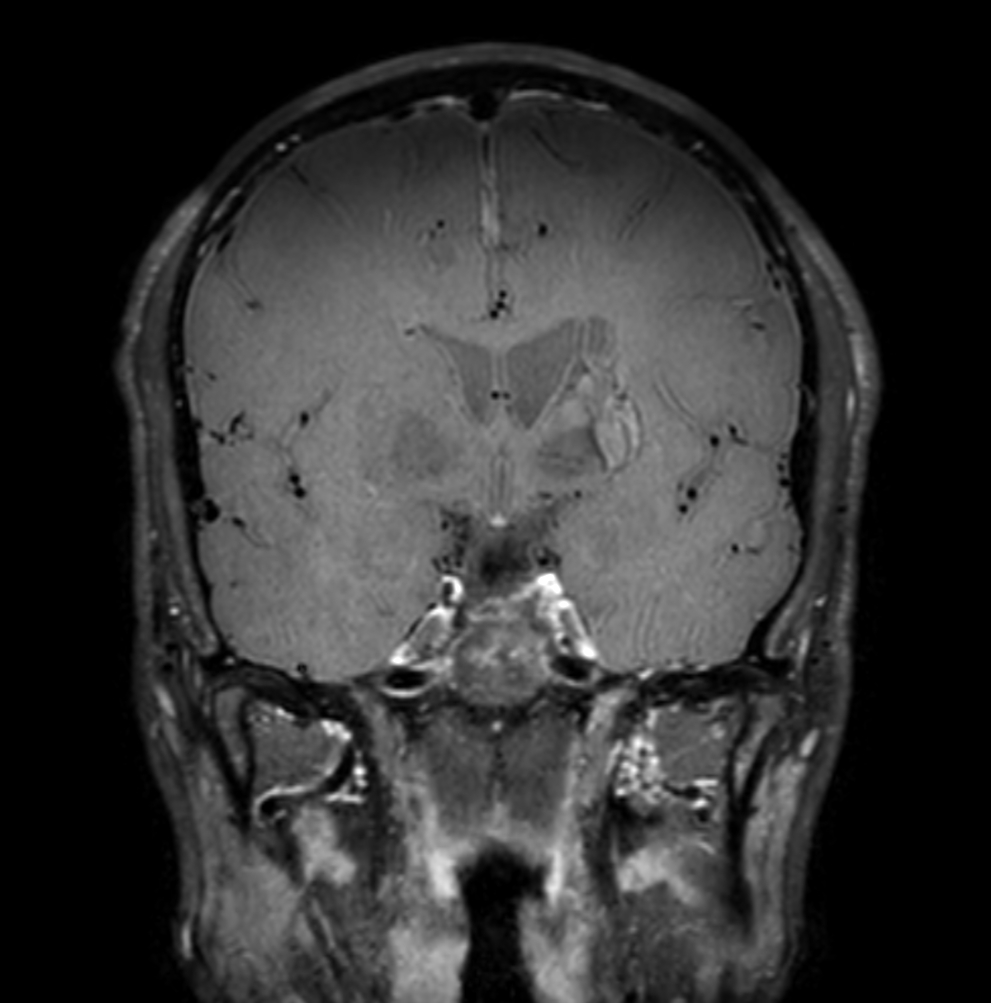

3D T1w TFE (post-gado)